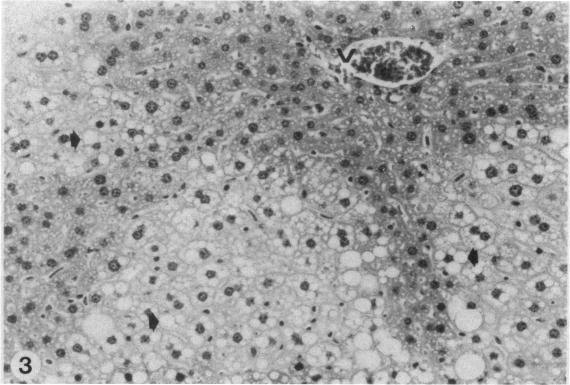

A recent study of the ability of chloroform in drinking water to produce cancer reported that male Osborne-Mendel rats developed renal tumors, but that female B6C3F1 mice failed to develop hepatocellular carcinomas. The results obtained in the male Osborne-Mendel rats were comparable to those observed in an earlier study sponsored by the National Cancer Institute (NCI). On the other hand, the lack of an increased incidence of hepatocellular carcinomas in female B6C3F1 mice was in sharp contrast to previously reported results. The doses of chloroform used were comparable to that which produced an 85% incidence in the NCI study. We have investigated the extent to which the vehicle might be responsible for the different results in these two studies by examining the differential effects of chloroform when it was administered by gavage using corn oil versus a 2% Emulphor suspension as the vehicle. Male and female B6C3F1 mice were administered chloroform at 60, 130, and 270 mg/kg per day for 90 days. At sacrifice, body and organ weights were measured, and blood was recovered to perform the following serum chemistry measurements (in order of priority): glutamate oxalacetate transaminase (SGOT), lactate dehydrogenase (LDH), blood urea nitrogen (BUN), and triglyceride (TG) levels. The liver was sectioned for histopathological examination. Chloroform increased SGOT levels significantly only when administered in corn oil at a dose of 270 mg/kg in both male and female mice. It had no effect on LDH activity. There was a small increase in BUN when chloroform was administered in corn oil, but not when administered in 2% Emulphor. When administered in corn oil, chloroform significantly decreased serum TG levels but was without effect on this parameter when administered in 2% Emulphor. Chloroform decreased body weight and increased liver weight with both vehicles, but the effects were significantly greater when it was administered in corn oil. Mice administered chloroform in corn oil displayed a significant degree of diffuse parenchymal degeneration (5 of 10 males and 1 of 10 females) and mild to moderate early cirrhosis (5 of 10 males and 9 of 10 females); significant pathological lesions were not observed in the animals administered corn oil without chloroform nor in mice receiving chloroform in 2% Emulphor. These data indicate that administration of chloroform by corn oil gavage results in more marked hepatotoxic effects than observed when it is provided in an aqueous suspension.(ABSTRACT TRUNCATED AT 400 WORDS)

最近一项关于饮用水中氯仿致癌能力的研究报告称,雄性奥斯本-孟德尔大鼠会发生肾肿瘤,但雌性B6C3F1小鼠未发生肝细胞癌。在雄性奥斯本-孟德尔大鼠中获得的结果与美国国立癌症研究所(NCI)早期资助的一项研究中观察到的结果相当。另一方面,雌性B6C3F1小鼠肝细胞癌发病率未增加,这与之前报道的结果形成了鲜明对比。所使用的氯仿剂量与NCI研究中产生85%发病率的剂量相当。我们通过研究氯仿以玉米油灌胃与以2%乳化剂悬浮液作为载体给药时的不同效果,来探究载体在这两项研究中导致不同结果的程度。给雄性和雌性B6C3F1小鼠每天按60、130和270mg/kg的剂量给予氯仿,持续90天。处死时,测量体重和器官重量,并采集血液进行以下血清化学测量(按优先顺序):谷草转氨酶(SGOT)、乳酸脱氢酶(LDH)、血尿素氮(BUN)和甘油三酯(TG)水平。将肝脏切片进行组织病理学检查。仅当雄性和雌性小鼠以270mg/kg的剂量用玉米油灌胃给予氯仿时,氯仿才会显著提高SGOT水平。它对LDH活性没有影响。当用玉米油给予氯仿时,BUN略有升高,但用2%乳化剂给药时则没有。当用玉米油给药时,氯仿显著降低血清TG水平,但用2%乳化剂给药时对该参数没有影响。两种载体给药时氯仿都会降低体重并增加肝脏重量,但用玉米油给药时效果更显著。用玉米油给予氯仿的小鼠出现了显著程度的弥漫性实质变性(10只雄性中有5只,10只雌性中有1只)和轻度至中度早期肝硬化(10只雄性中有5只,10只雌性中有9只);在未给予氯仿的玉米油给药动物以及接受2%乳化剂氯仿给药的小鼠中未观察到明显的病理病变。这些数据表明,与以水悬浮液形式给药相比,用玉米油灌胃给予氯仿会导致更明显的肝毒性作用。(摘要截断于400字)